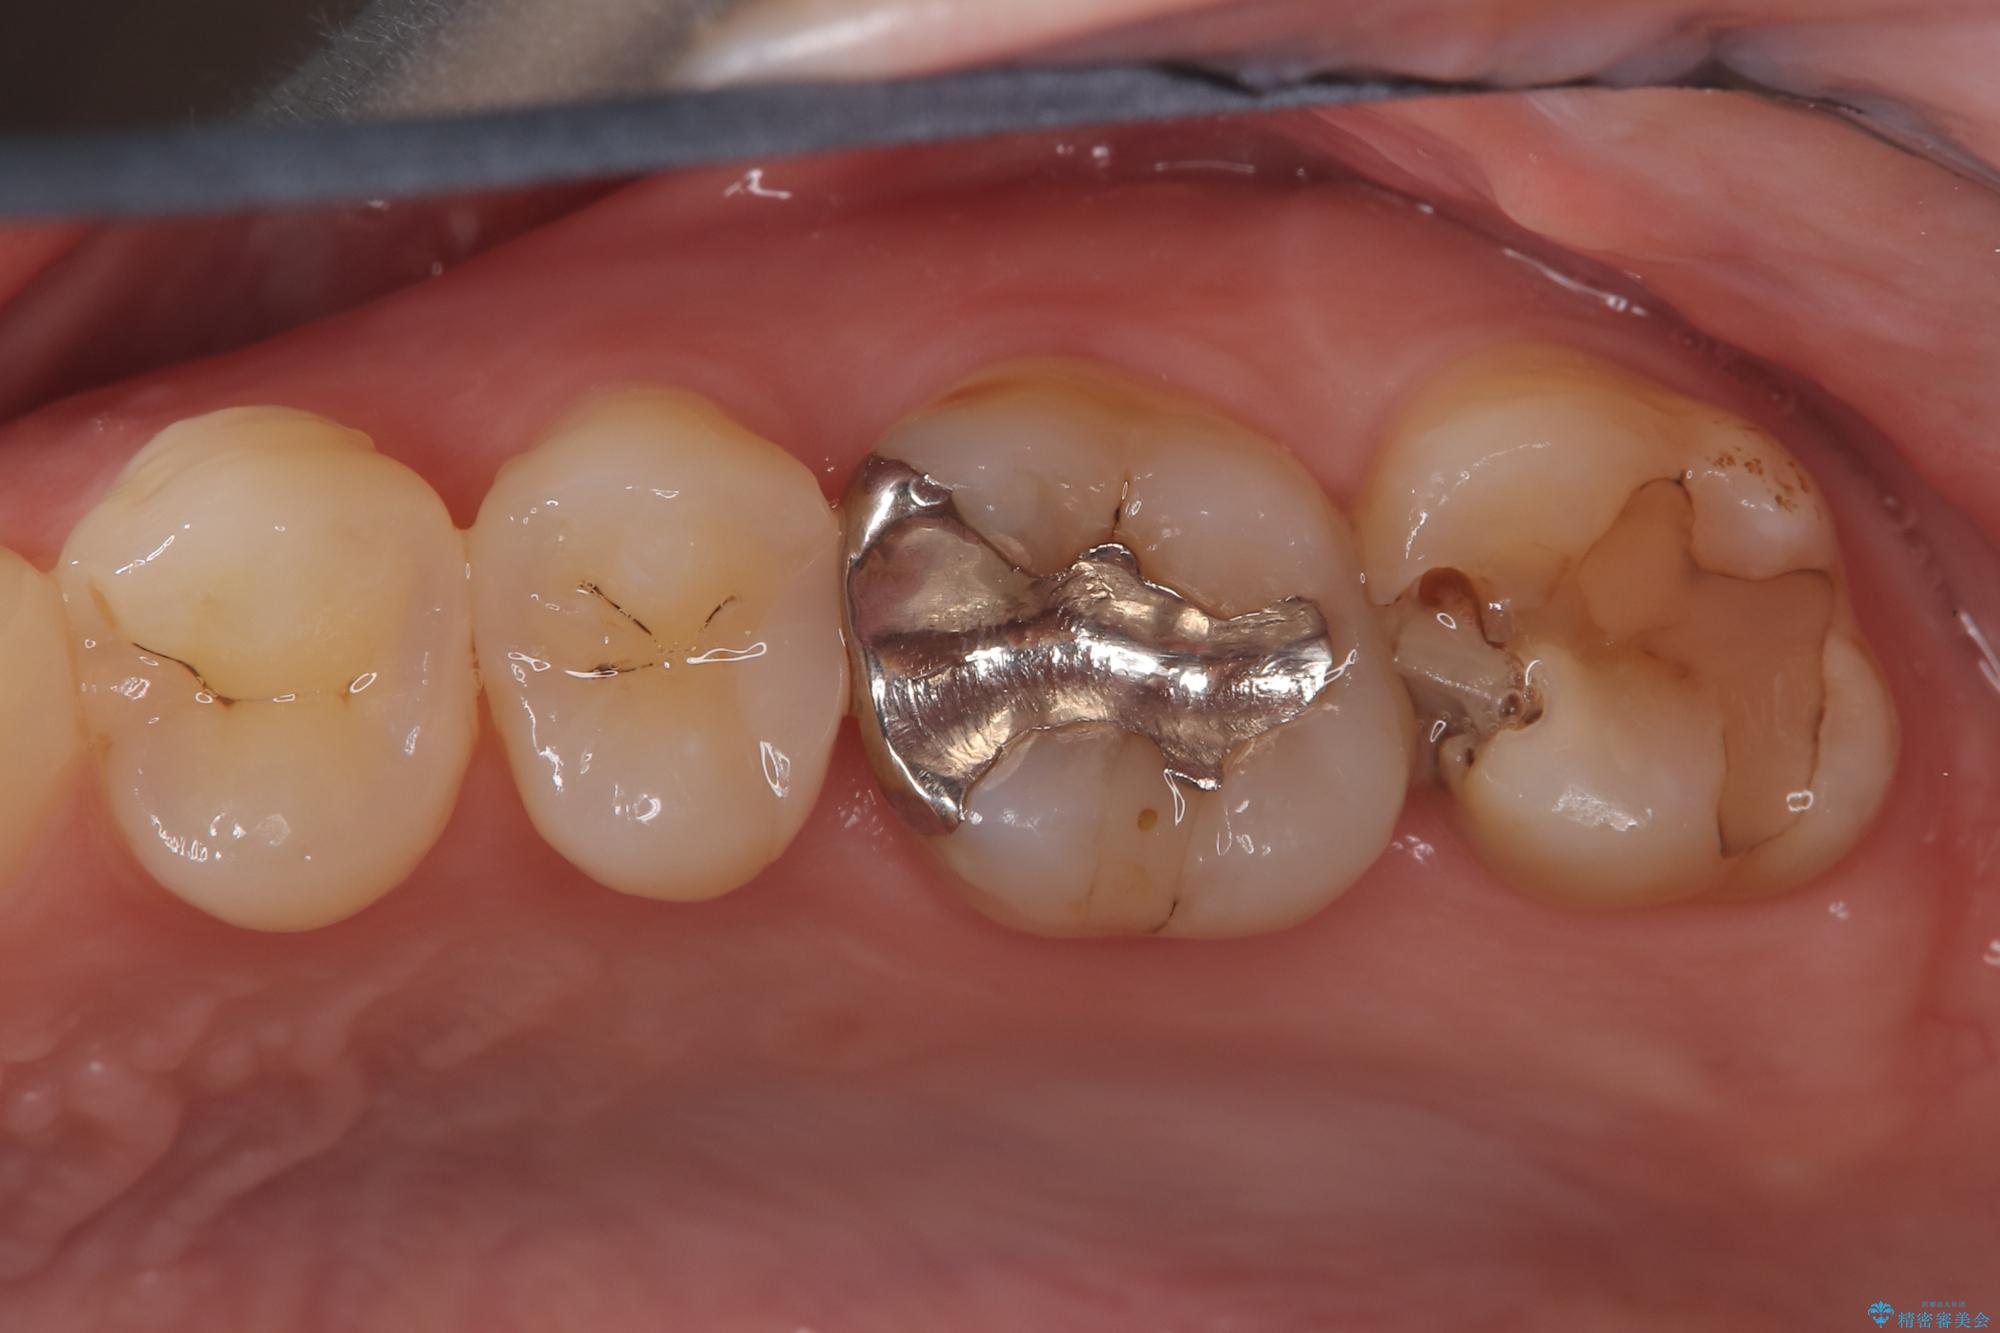

- 「冷たいものが強くしみる」という主訴でご来院されました。精密な診査の結果、虫歯が非常に深く、通常であれば神経を全て抜く「抜髄(ばつずい)」が必要な状態でした。しかし、神経を抜くと歯の寿命が縮まってしまうため、今回は神経の一部を温存する**「部分的断髄法(VPT)」**を提案しました。高い殺菌性と封鎖性、そして組織の再生を促す効果を持つMTAセメントを使用して神経を保護し、最終的には強度と審美性に優れたセラミックで修復する計画を立案しました。

部分的断髄法(MTAの使用): ラバーダム防湿を行い、無菌的な環境下で虫歯を慎重に除去。神経の露出を確認した後、炎症を起こしている一部の神経のみを除去し、残りの健全な神経を保護するためにMTAセメントを充填しました。これにより、神経の機能を維持し、歯を内部から守ることが可能となりました。